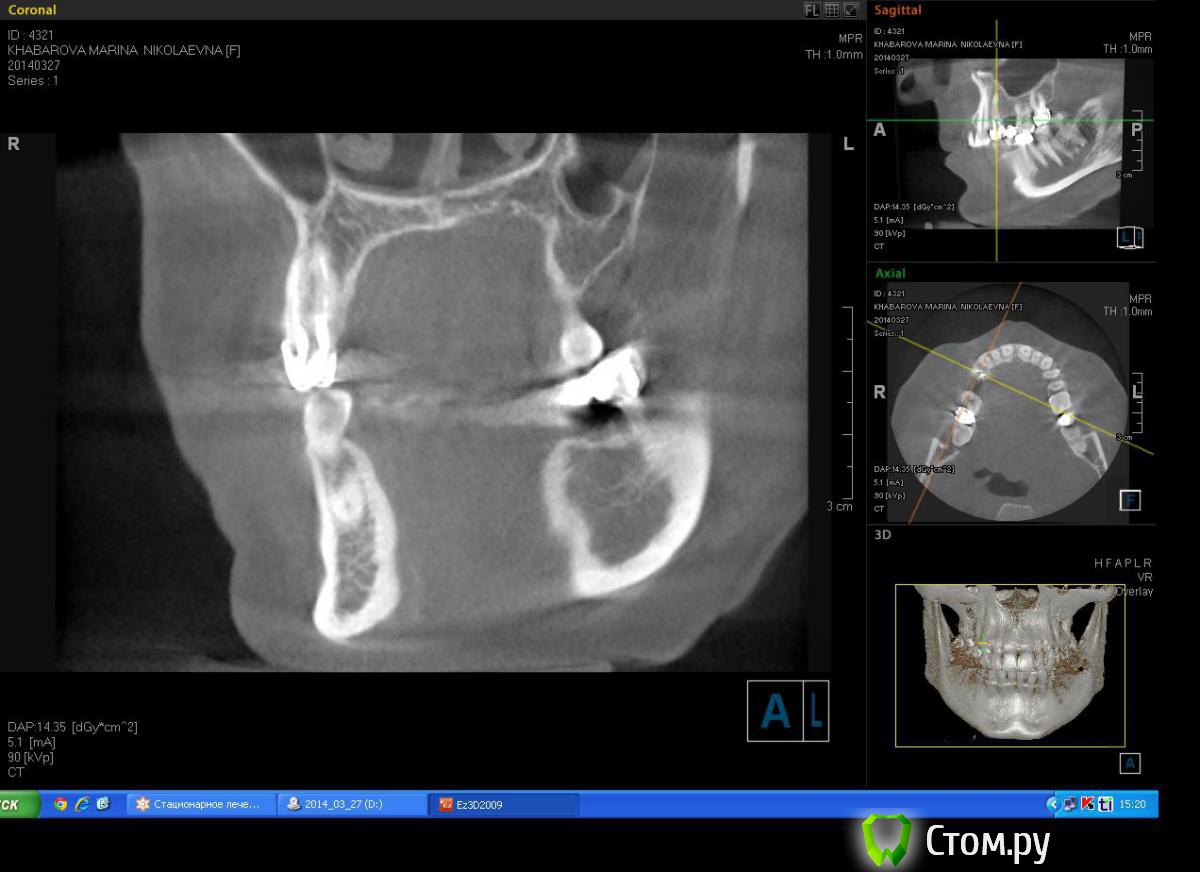

Milanomoda Опубликовано 22 апреля, 2014 Поделиться Опубликовано 22 апреля, 2014 Здравствуйте, уважаемые коллеги. Вообщем обратилась за помощью пациентка - в области 14 зуб, от него консоль на 15, посоветовавшись с ортопедом, приняли решение удалить 14 зуб и одномоментно в лунку имплант, в это же посещение имплантация в области 15. Подскажите пожалуйста с тактикой, можно ли в данном случае рассматривать одномоментную методику имплантации ? Заранаее с пасибо ) Снимки КТ прикладываю. Ссылка на комментарий

DShu Опубликовано 22 апреля, 2014 Поделиться Опубликовано 22 апреля, 2014 4,2 думаю им там тесновато будет. 4,5 тем более.На 14 я бы поставил 3,75*16 (или на 13) на 15 - 3,75*10 бикортикально. Сразу формики, вокруг - графт или без него, кто как любит) 3 Ссылка на комментарий

Milanomoda Опубликовано 22 апреля, 2014 Автор Поделиться Опубликовано 22 апреля, 2014 4,2 думаю им там тесновато будет. 4,5 тем более.На 14 я бы поставил 3,75*16 (или на 13) на 15 - 3,75*10 бикортикально. Сразу формики, вокруг - графт или без него, кто как любит)Если в области 15 делать бикартикальную фиксацию то без синуса(закрытого) не обойтись, а если делать без синуса - то при нагрузке мне кажется слизистая гайморовой среагирует, не даром же от анатомических образований рекомендуют около 2 мм отступать... Ссылка на комментарий